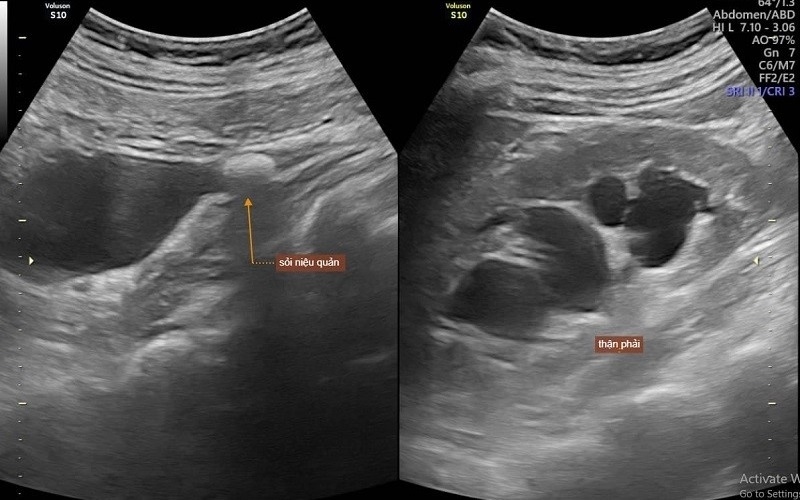

2.5. Siêu âm thận – hệ tiết niệu

– Ưu điểm: Nhanh, không xâm lấn, không dùng tia X

– Phát hiện: Sỏi thận – niệu quản, ứ nước thận, u thận, u bàng quang, đánh giá kích thước và hình thái thận

– Thường dùng đầu tiên trong khảo sát tiết niệu

Chẩn đoán thận – tiết niệu bằng phương pháp siêu âm được áp dụng phổ biến